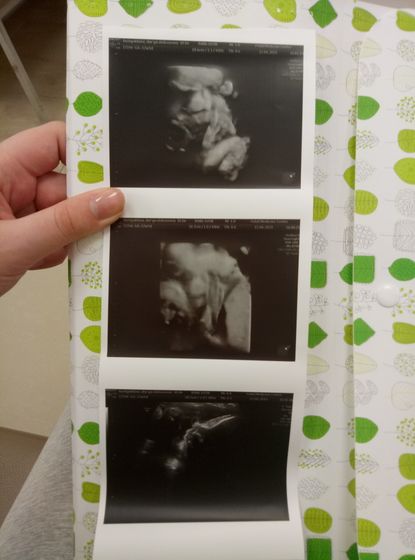

Всем привет) прошли скрининг, у сына всё хорошо. Щеки очень знатные и врач сказала, что паркнь очень серьезный и хмурый? Обвитие пуповины уже нету, снял сам?Но поставили многоводие ( неделю назад его не было) подскажите чем страшно? Как лечили? Прием врача только 22 апреля и хочется немного успокоится, что не все так страшно. Весит кроха 2562 гр. А ещё у меня пошли отеки, особенно ноги! Если сама до приема врача не справлюсь наверное придётся ложиться (( Но надеюсь на дневной стационар, не хочу лежать там? А как у вас дела?) Как выходные?)

Мне кажется на мужа, мама думает на неё ( да возможно, что-то есть), но нос точно свекрови ? у нас у всех острые носики, а тут такая картошечка?

Спасибо ? еще фото и видео на флешке? красивые, цветные) но сил пока нет до ноута дойти) связки болят после такого похода)))

Я ворчала, что ещё лучше хочу ? сын носом уткнулся в пуповину, ждали долго и ела сладкое, но так и не подвинул её ? хотела полностью мосю)))